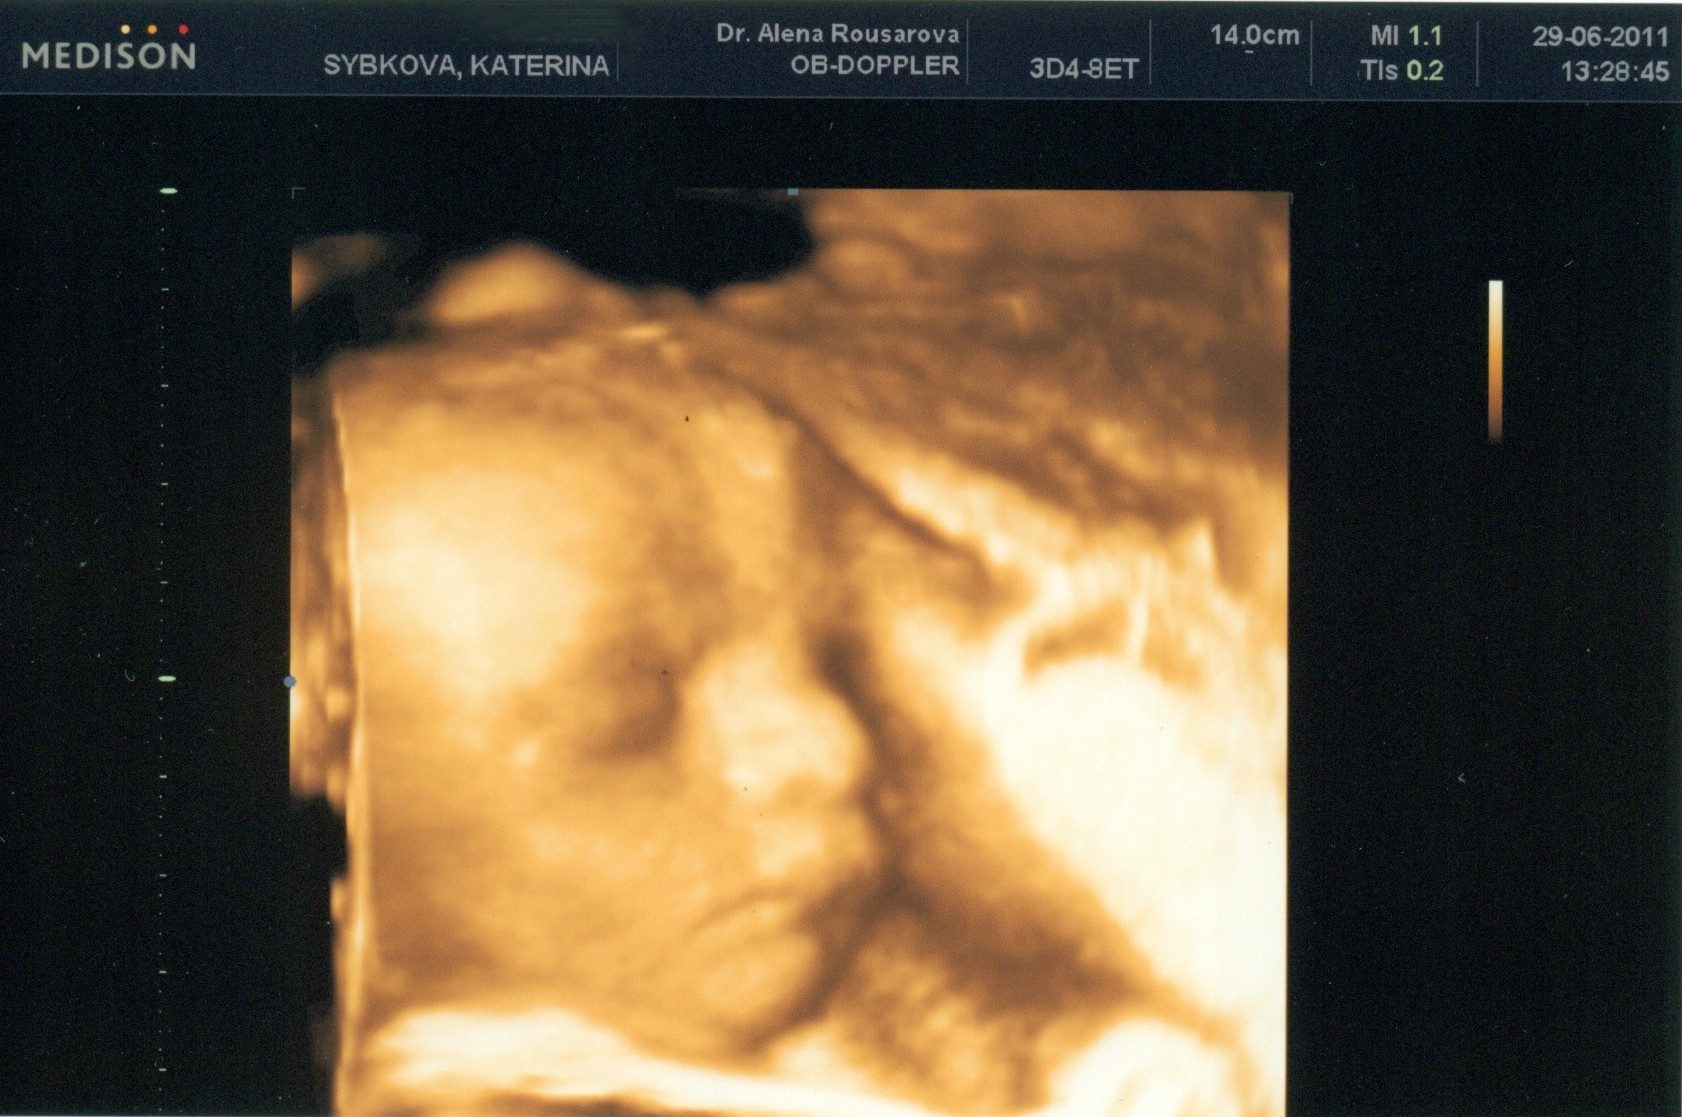

Jinak jsem včera byla na tom 3D ultrazvuku. Byl to fakt zážitek, dokonce jsem i zaslzela. Ze začátku to vypadalo, že malej nebude vůbec spolupracovat, dával si před obličel obě ručičky, ale pak se umoudřil a dokonce dělaj i pěkné ksichtíky, to má asi po mě

Ale je to celej tatínek. Nosánek, tvářičky, bradička a dokonce se mu dělá stejný ďolík ve tváři. Manžel je na to samozřejmě pyšnej